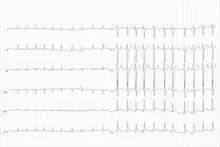

| Telemetry strip of a 44-year-old female with asymptomatic sinus pause found while admitted for mildly symptomatic COVID-19 pneumonia. | |

The primary 12-lead electrocardiogram (ECG) finding in sinus node dysfunction is inappropriate sinus bradycardia.[7] Sinus node dysfunction can also present with sudden sinus arrest with or without junctional escape, sinoatrial block, prolonged asystolic period followed by tachycardias, or tachycardia-bradycardia syndrome presenting as various atrial arrhythmias such as atrial fibrillation, flutter, tachycardia, or paroxysmal supraventricular tachycardia.[7][5]